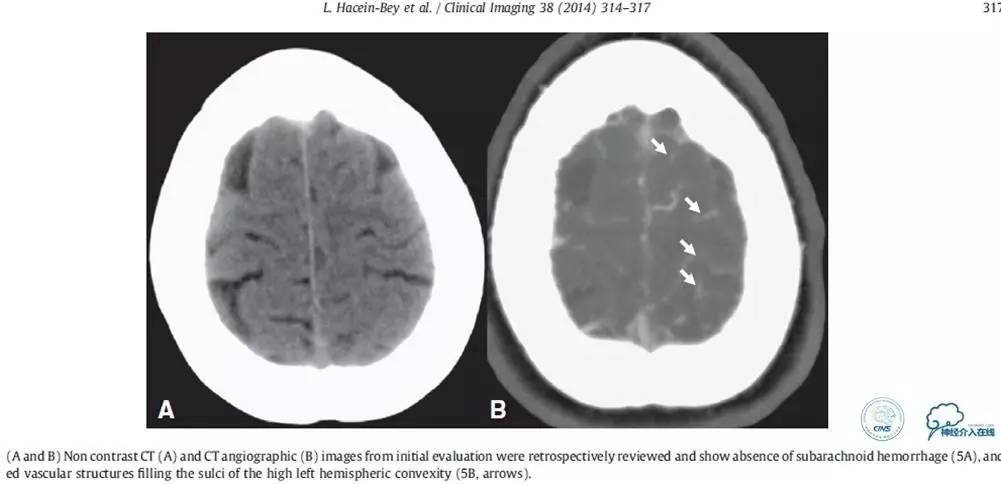

▼2015-06-05颅脑CT

患者时间窗内,发病3h开始静脉溶栓。rt-PA9mg/kg,70mg,7mgIV;63mg微量泵注入1h。期间患者症状改善不明显。观察时间后,仍无改善。遂介入交接治疗。

2015-06-05脑血管造影:左侧颈内动脉闭塞。

评估患者侧支循环,考虑患者发病时间超过6个多小时,未行血管内治疗。

▼2015-06-05颅脑MRI

▼颅脑CT

▼2015-06-13颅脑CT

患者症状稳定,遗留有失语及右侧肢体活动不灵。